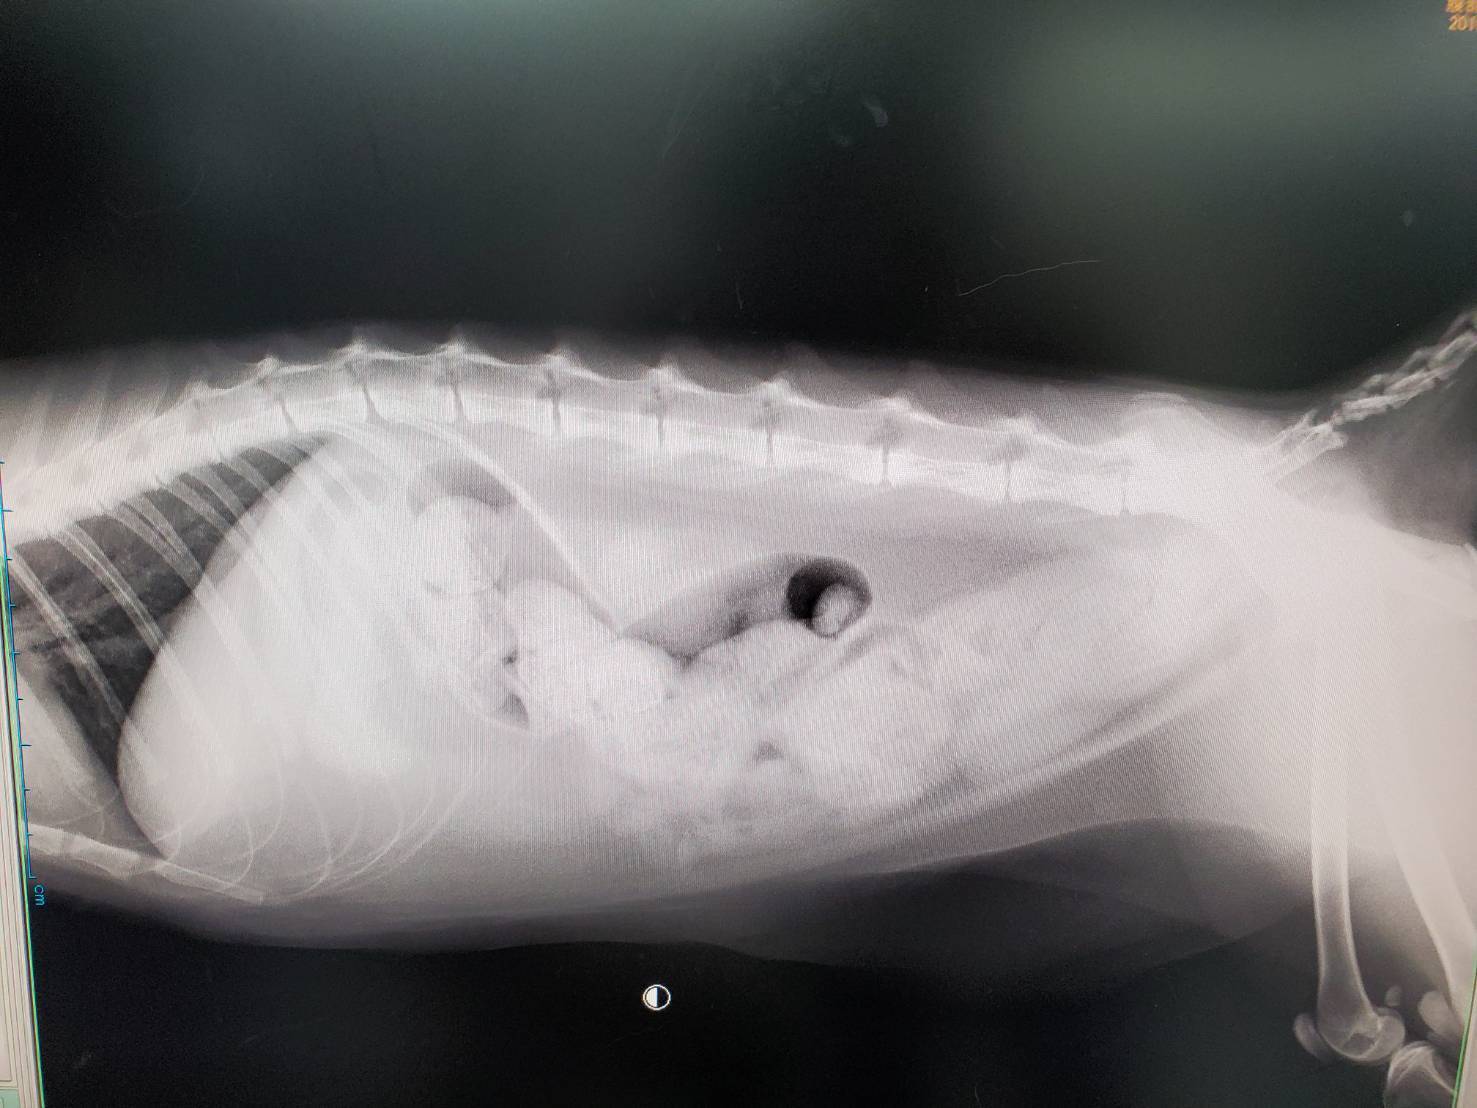

綺麗な長毛猫のまるちゃんを里親募集するはずが、保護後しばらくすると突然 後肢に激しい痛みと麻痺が起こりました。検査の結果、心臓に重篤な病気があることが分かりました。根治することのない病気、心筋症と診断されてしまいます。

まるちゃんの場合、心臓の中にできた血栓が後肢の付け根の動脈に詰まり、命が危険な状態でした。幸い一命はとりとめましたが、血行が途絶えた足先はやがて壊死し、脱落してしまいました。

血栓の治療と、骨がむき出しになった足の皮膚の再生治療が始まりました。欠かすことのできない心臓病の治療薬や抗凝固薬の内服、朝晩2回の抗凝固剤の注射、3日に1回の皮膚再生を促すドレッシング治療、特別食給餌などです。こういった治療を続けないと、まるちゃんは生きていけません。一時は容態が悪化し酸素室に入り、安楽死を決めたこともありましたが、安楽死処置の当日 気丈に起き上がるまるちゃんを見て、命をあきらめることはできませんでした。

現在まるちゃんは、再発や感染の危険と戦いながら、連日の治療のため病院で生活しています。両後肢は麻痺が残っていますが、 骨を覆うようにかなりの皮膚が再生され、厚く包帯を巻いてもらった足で歩くことができるようになりました。